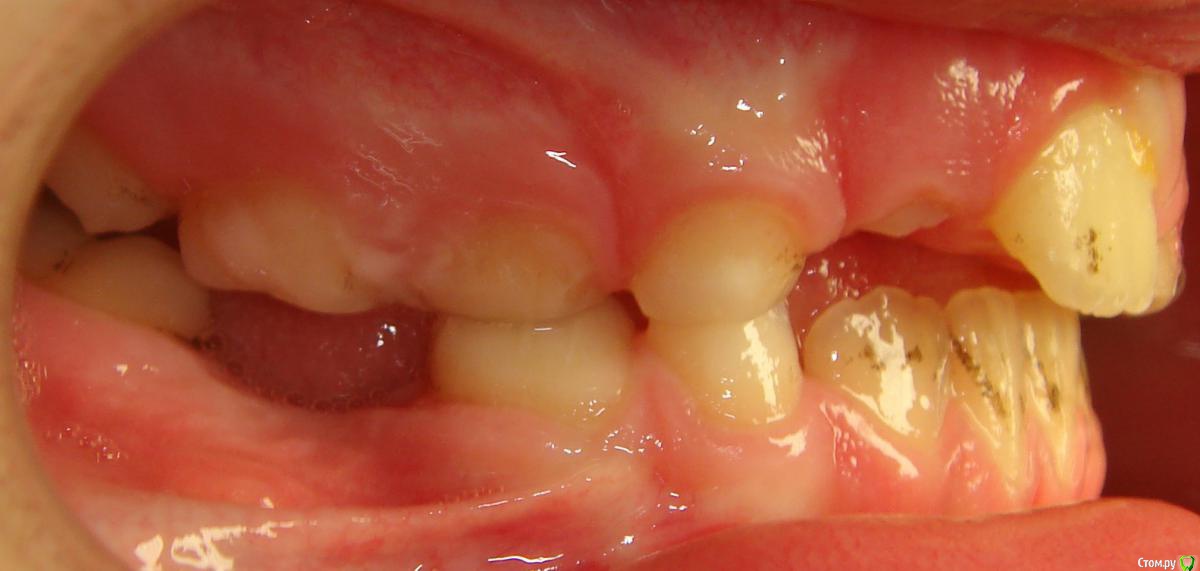

Opdihatop Опубликовано 9 января, 2017 Поделиться Опубликовано 9 января, 2017 Здравствуйте, коллеги! Хотел бы узнать ваше мнение по пациентке. Девочке 7 лет. План лечения в общем мне ясен и понятен. Меня интересует вопрос, когда лучше в данном случае убирать сверхкомплектный премоляр в области 21 зуба, потому что он начал двигать ц.л. вправо. Заранее спасибо! Ссылка на комментарий

Yana guapa Опубликовано 13 января, 2017 Поделиться Опубликовано 13 января, 2017 убрать молочный ц. резец. подождать 6-8 месяцев хотя бы (лучше год) - все ростковые зоны уже значительно выше будут, хирург не задет уже.сделать КТ. и удалить сверхкомплектный. Дать возможность опуститься ц. резцу.сильно долго ждать (до полного формирования корней) не вижу смысла. Очень похожа ситуация была у моей девочки (такое же расположение). - очень долго не хотел ц. резец спускаться. Райц-терапия в помощь)) вышел)) Ссылка на комментарий

Yana guapa Опубликовано 16 января, 2017 Поделиться Опубликовано 16 января, 2017 А что вы для райцтерапии в данном случае использовали?обычный протез с зубом (у нее 2.1 был) . активно кушать с протезом. (Прорезался месяцев черзе 7-8, очень высоко был)Бывало, что зуб годами не выходил, родители обратились к ортодонту, и после изготовления такого протеза зуб выходил от 3 дней до 1 месяца. у всех по-разному. Ссылка на комментарий